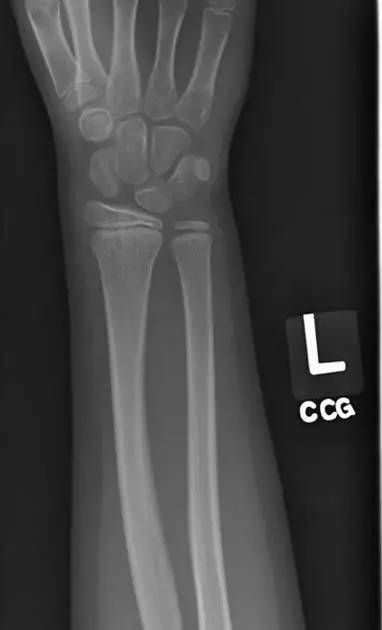

10. Galeazzi 骨折(盖氏骨折)

桡骨干下 1/3 骨折合并尺骨小头脱位。

盖氏骨折正侧位(来源:Orthobullets)